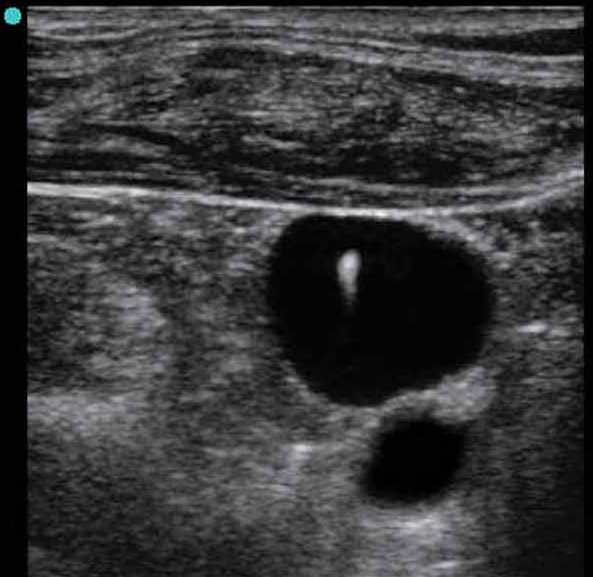

M-Turbo: IJV Short Axis with Needle